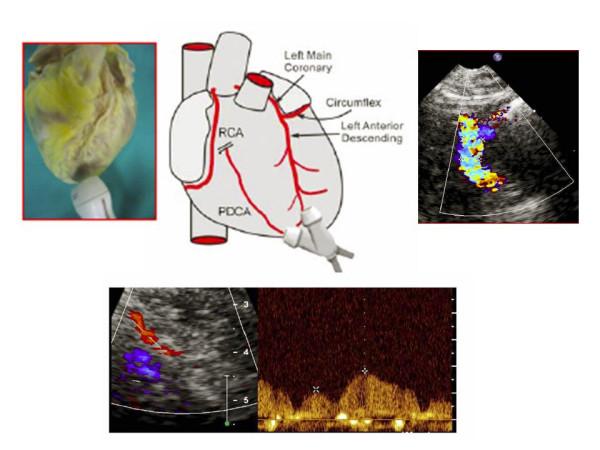

The aim of this paper is to highlight coronary investigation by transthoracic Doppler evaluation. This application has recently been introduced into clinical practice and has received enthusiastic feedback in terms of coronary flow reserve evaluation on left anterior coronary artery disease diagnosis. Such diagnosis represents the most important clinical application but has in itself some limitations regarding anatomical and technological knowledge. The purpose of this paper is to offer a didactic approach on how to investigate the different segments of left anterior and posterior descending coronary arteries by transthoracic ultrasound using different anatomical key structures as markers. We will conclude by underlining that, nowadays, innovative technology allows complete evaluation of both major coronary arteries in many patients in a resting condition as well as during pharmacology stress-tests, but we often do not know it.

https://cdn.ncbi.nlm.nih.gov/pmc/blobs/fc7a/2268663/3f0fee3d1088/1476-7120-6-7-1.jpg